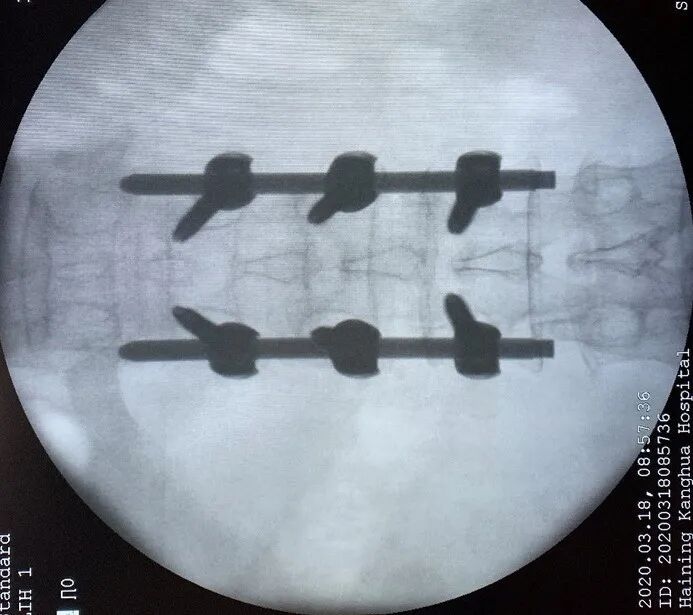

54岁的丁先生,在工地干活时不慎从2米高的高处坠落,臀部着地,当时丁先生只觉得腰部剧痛,不能自如活动,随即由工友送到了海宁康华医院骨2科就诊。 经过CT检查,发现丁先生腰1椎骨折,压缩了约1/2,需要立即采取手术。 丁先生考虑到自己是家中重要的劳动力,强烈要求采取创伤小、恢复快的方案进行治疗,以便自己尽快恢复工作。骨2科团队经过认真研究,决定采用微创小切口的方式在脊柱后路用钉棒固定丁先生因骨折压缩的腰1椎体。最终手术顺利完成。 术后经过复查,CT图像提示腰椎高度回复,内固定位置良好,一周后即可下床。 康华医院骨2科主任、副主任医师陈杰介绍,传统处理腰椎骨折手术需要切开皮肤,剥离肌肉,显露椎体结构后,植入椎弓根螺钉固定,存在切口长、椎旁肌肉剥离广泛、术中出血多、术后切口引流量大、术后切口疼痛、恢复期长等一系列的问题。 而像丁先生这样采取经皮微创植入椎弓根钉棒固定的手术,因其手术创口小(约1cm*6),术中出血少,不剥离椎旁肌肉,术后切口无需引流,无术后切口疼痛,可早期下地进行功能恢复,是近年来发展起来一项技术,也是近年来治疗腰椎滑脱、胸腰椎骨折、椎管狭窄等脊柱疾病采用的一种手术方式。 因为是微创技术,对手术技术要求比传统手术方式更高,术前需要非常周密的计划,根据患者的影像资料做非常精确地测量和定位,更需要手术医生具有非常娴熟技术,因此之前只有一些三甲大医院才有开展。近年来,骨2科在陈杰主任带领下,刻苦钻研,不懈追求,不断精进,希望能以更精湛的技术,温馨的服务,竭力为广大患者解除病痛。